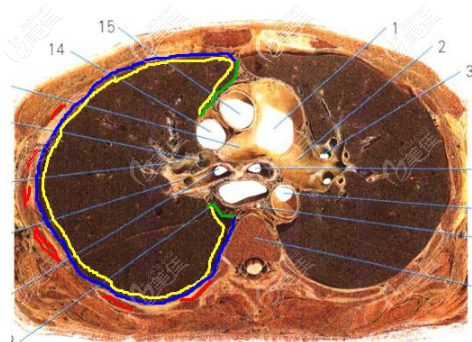

隆鼻取肋软骨时容易戳破胸膜引起气胸,这是真的吗?

b1546 G0 V0

取肋软骨做隆鼻手术,比较大的一个风险就是可能会发生气胸,这让很多人望而却步,那么到底容不容易发生气胸呢?我们一起来看看!